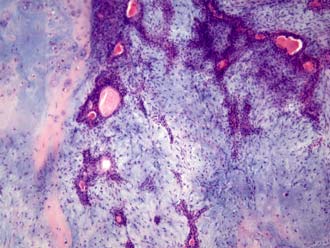

При гистологическом исследовании ткани опухоли слюнной железы нужно определить ее тип. Выделяют:

- Мономорфные опухоли — состоят из однотипных железистых клеток (базальноклеточные, светлоклеточные, аденолимфома), имеют хорошо выраженную капсулу;

- Плеоморфные (полиморфные) — включают разнообразные клетки протокового типа, миоэпителий, элементы концевых отделов желез, но все они достаточно хорошо дифференцированы.

Оба типа аденом могут протекать с врастанием опухолевой ткани в капсулу железы, с чем можно связать возможность рецидива при нерадикальном их иссечении. Плеоморфная аденома при росте способна оттеснять окружающие ее мышцы, сдавливать нервы и сосуды. Риск озлокачествления доброкачественной аденомы слюнной железы довольно низок: трансформация в рак происходит у нескольких пациентов из ста.